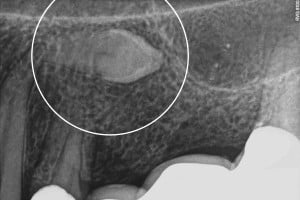

Rozpoznanie zęba zatrzymanego opiera się na badaniu rentgenowskim.